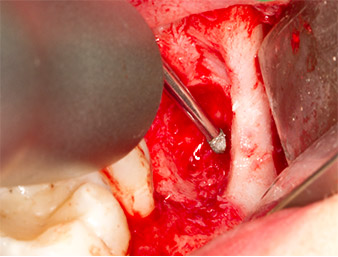

Using an instrument for periodontal debridement (Piezomed P1), the periodontal ligament space of the radix relicta was then widened minimally (Fig. 8).

The same activated instrument was inserted into the root canal and loosened the fragment as a result of its micro-oscillating vibrations (Fig. 9, 10).